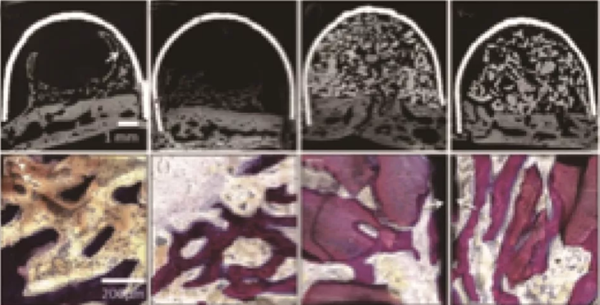

因為PRF中含有生長因子,而體外實驗也證明了這些生長因子具有一定的促進成骨效果。學者也將其應用到了促進成骨的動物實驗中,Knapen等在兔的顱骨中研究了PRF的促進成骨效果[5],結(jié)果在組織學和組織形態(tài)定量學的分析中(圖2、3)都沒能發(fā)現(xiàn)PRF有任何附加的影響。

Nejat在上頜竇外提升術(shù)中研究了PRF促進成骨的效果[6],在實驗中對照單獨使用Bio-oss和Bio-oss聯(lián)合PRF在上頜竇提升術(shù)中的應用,在6個月的愈合期之后,對新生骨進行組織學和組織形態(tài)定量分析(圖4),發(fā)現(xiàn)兩組沒有差異。這就說明了PRF的使用并不能帶來更多更好的成骨效果。